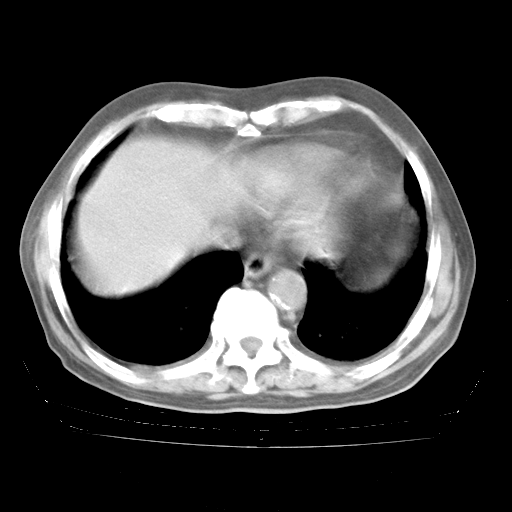

4月28日肺部CT——再次出现类似去年5月9日——透光度降低,“间质性”改变。